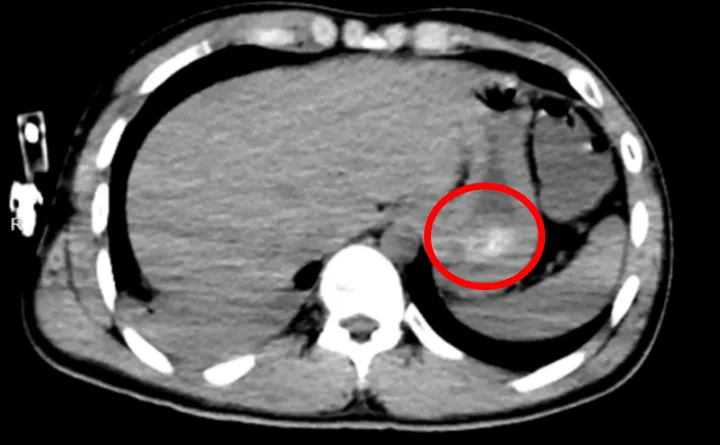

“服药已超14小时,血药浓度却持续升高,这不符合常规药物吸收规律。”北大深圳医院中毒快反团队迅速警觉,经全腹CT检查证实,林浩胃底存在大量团块状高密度影,也就是常规洗胃无法清除的“药石”,同时胸部CT显示其双肺出现渗出性病变,已引发吸入性肺炎。“罪魁祸首就是胃里持续释放毒性的药石,叠加吸入性肺炎,随时可能导致多器官衰竭。”急诊科副主任杨莹解释。